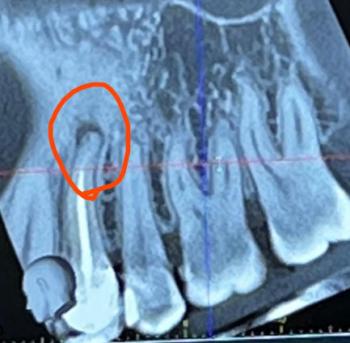

Apical Infection After Root Canal - CBCT Dental Case

Dental Case Analysis – Apical Infection After Root Canal Treatment

This CBCT image shows the anterior maxillary region with multiple natural teeth. A well-defined radiolucent lesion is visible at the root apex of a previously treated tooth (circled area), indicating a persistent apical infection. Surrounding bone shows early structural changes.

Clear apical radiolucency at root tip

Loss of normal bone trabeculation

Root canal filling present but likely incomplete

Lesion confined but expanding

Adjacent teeth currently unaffected

Chronic apical periodontitis

Failed or compromised root canal treatment

Localized periapical bone loss